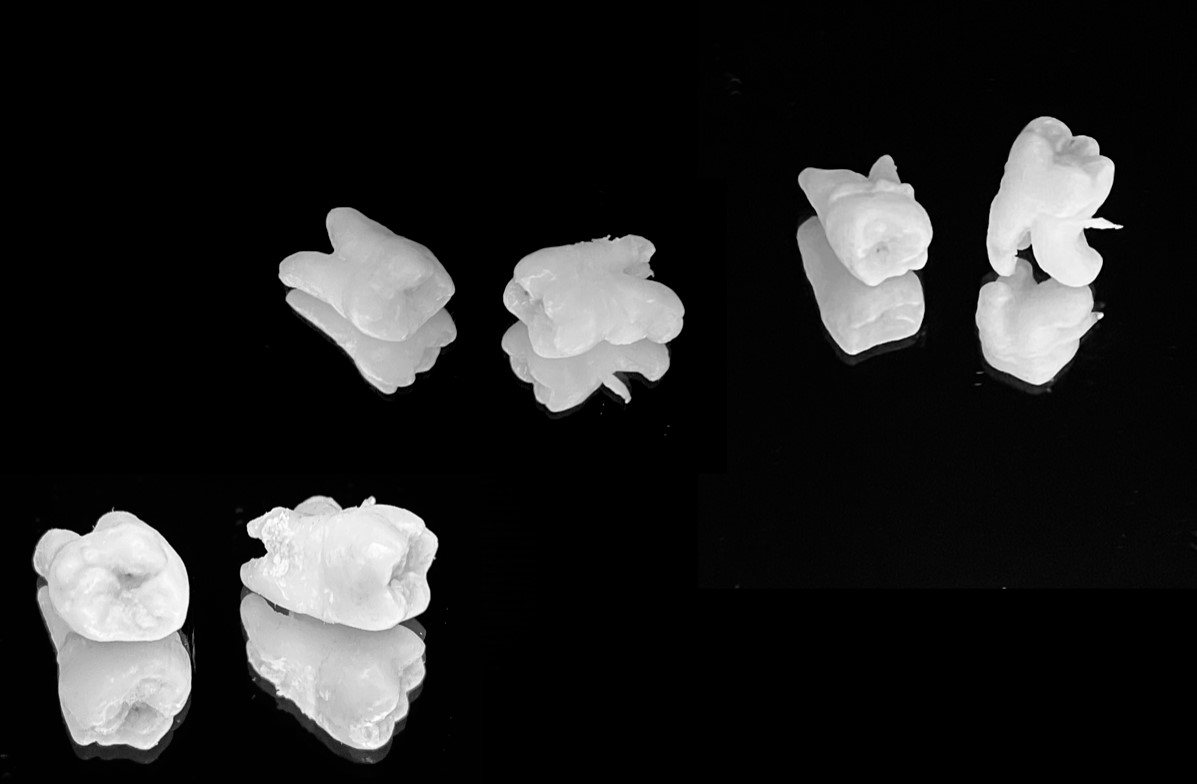

Профессиональная гигиена полости рта5 000 - 7 000 ₽

Профессиональная гигиена полости рта5 000 - 7 000 ₽ Терапевтическое лечение (пломба)от 5 000 ₽

Терапевтическое лечение (пломба)от 5 000 ₽ Эндодонтическое лечение15 000 - 22 000 ₽

Эндодонтическое лечение15 000 - 22 000 ₽ Удаление4 000 - 10 000 ₽

Удаление4 000 - 10 000 ₽ Имплантация, пластика костнаяот 35 000 ₽

Имплантация, пластика костнаяот 35 000 ₽ Протезирование зубовот 25 000 ₽

Протезирование зубовот 25 000 ₽